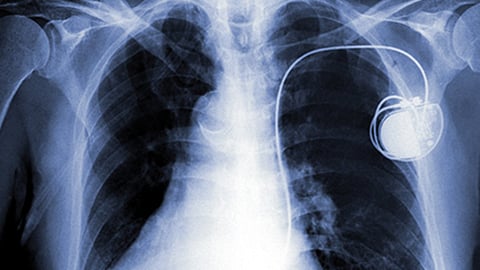

¿Podría tu reloj inteligente interferir con tu marcapasos?

Un nuevo estudio revela que los relojes inteligentes y otros monitores de bienestar pueden interferir con los marcapasos y otros dispositivos cardíacos implantables.